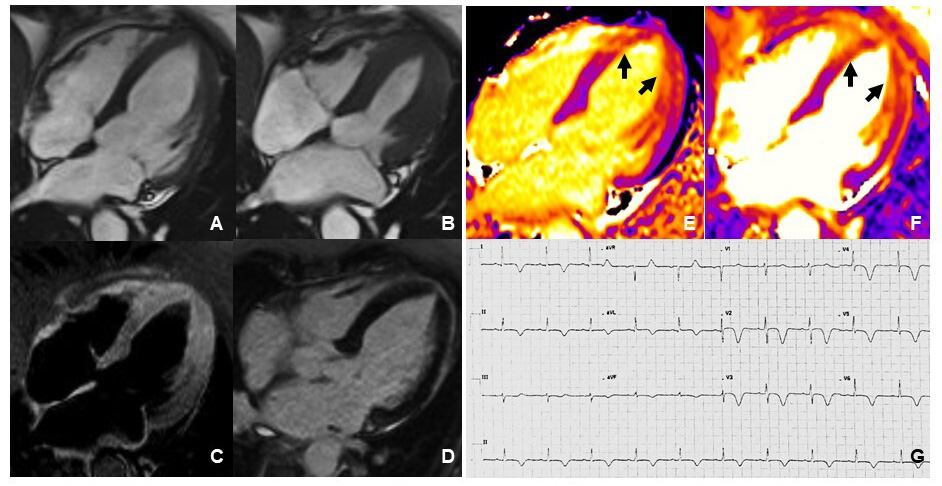

In conclusion, ECG is a simple but useful tool in patients with TTS that should always be performed in the follow-up evaluations, especially when CMR or more advanced echocardiographic methods (e.g., speckle tracking echocardiography) are not available. Fig. 1 shows the typical evolution of ECG changes in TTS.

Fig. 1.Left precordial ECG leads (V4-V6) of a TTS patient. ECG recorded at the onset of symptoms (A). ECG recorded at discharge, 5 days from the acute event (B). ECG recorded after 3 months from the acute event (C). ECG recorded after 1 year from the acute event (D). During the acute phase, the ECG shows non-specific abnormalities of ventricular repolarization. Widespread inversion of the T-wave occurs during the subacute phase. The follow-up ECG recorded 3 months after discharge shows positivization of the T-wave but without complete recovery. The follow-up ECG recorded 1 year from the acute event shows complete recovery of ventricular repolarization with a higher voltage T-wave.